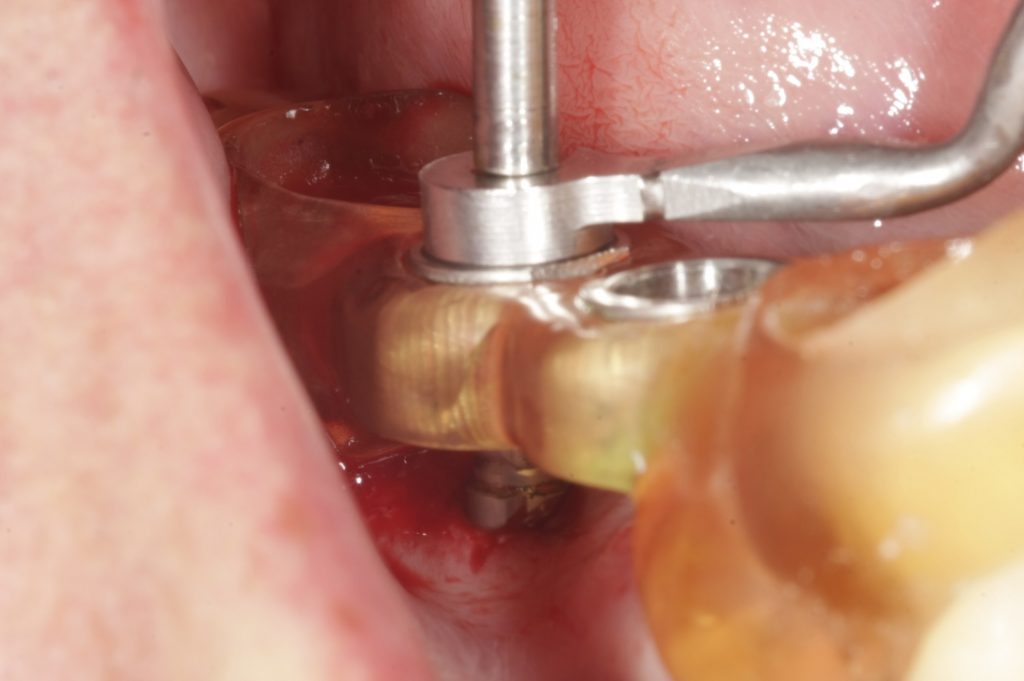

Autores: PRÓLOGO Asimismo, desde el punto de vista pedagógico, el profesional nobel en la materia tiene a su alcance la posibilidad de corregir cualquier posición implantaría en el ordenador, planear los provisionales y plasmarlos en la bio réplica antes de tocar al paciente a operar. Todos estos razonamientos nos llevan a presentar un caso de condiciones muy favorables para poner en práctica estos métodos como primer acercamiento a una Odontología Digital de alta calidad, con medios informáticos, que ya están presentes en la profesión de hoy en día, y será la protagonista única del futuro. Por otro lado, después de numerosos estudios que nos llevan a plantear el “gap” entre implante y pilar(abuttment), como principal responsable de la periimplantitis dado que la microbiota presente en el mismo es imposible de limpiar y en su presencia la cortical ósea reacciona reabsorbiéndose, nos ha llevado a utilizar implantes monobloc ya que los ejes implantarios y protéticos coincidían, y nos permitían su uso. Además, el circonio, ha mostrado a la luz de estudios muy recientes, una preservación y adhesión de los tejidos blandos superiores al titanio, tanto en su tratamiento de superficie de la rosca como a nivel gingival. DESARROLLO Paciente varón de 68 años, con antecedentes de radio/quimioterapia cinco años antes, con Rehabilitación Oral de los cuatro cuadrantes, con una Oclusión Mutuamente Compartida conservada, (REF.8) la que fracasa en el cuadrante 4, 19 años después. El mismo presentaba un puente de porcelana sobre circonio con pilares en 44 y 47, reemplazando el edentulismo de 45 y 46. Se produce la fractura del PM del 44, y ante una endodoncia antigua y corta, se decide implantar las zonas edéntulas, conservando temporariamente los pilares, hasta producida la oseointegración, para entonces también exodonciar el 44. DIAGNÓSTICO Tomamos impresiones del maxilar antagonista, Arco Facial Estático y realizamos montaje del mismo mediante la sistemática ARTEX. Producimos la relajación del músculo Pterigoideo Externo, para obtener la ORC (Oclusión en Relación Céntrica) mediante el método de Laminillas de Long, basado en el concepto de INERVACIÓN RECÍPROCA. Esto nos permitirá montar el maxilar inferior, tanto en su forma de: La primera para practicar la cirugía guiada y comprobar su eficacia, y el modelo de yeso para ser escaneado y confeccionar la GUÍA QUIRÚRGICA. La Biorréplica la obtenemos transformando los archivos DICOM que nos da el CBCT en archivos STL, y a partir de ellos, mediante una tecnología de PROTOTIPADO RÁPIDO, la obtención de un objeto físico en 3D a través de la aglutinación selectiva de una sucesión de capas de polvo. Procedemos a montar la biorrèplica y el modelo de yeso del caso. Podemos verificar la exactitud de las medidas del hueso residual en la bio réplica y compararlas con el scanner. Arrojando un resultado de 8,5 mm de cortical externa a cortical externa. Pudiendo también medir la distancia hasta el dentario. y comparar gracias a la ventana lateral de la biorréplica Dándonos 22mm de distancia. Con lo cual deducimos que implantes de 4,1mm por 12 mm serán perfectamente rodeados de hueso. Medimos también la distancia desde oclusal del antagonista, hasta el hueso desnudo. Lo mismo que, mediante la utilización de la guía radiológica, con un material radiolúcido colocado en gingival de la misma, podemos medir la altura de la encía. Con lo cual podemos calcular la altura del pilar. Es entonces cuando con el programa COC Diagnostix se realiza la programación final: Obteniendo no solo la ubicación, largo, ancho y ángulo de los implantes sino también los provisionales mediante CAD CAM. Ya entonces podemos hacer la práctica quirúrgica en la bio réplica, mediante la guía quirúrgica, instalando los implantes de prueba que no serán los de circonio, ya que la casa no cuenta con ellos, pero si otros de las mismas dimensiones. TRATAMIENTO Entramos ya en la cirugía propiamente dicha. Antisepsia de la zona a operar y zonas anexas. Comprobación del perfecto ajuste e inmovilidad de la G.Q. en boca durante la cirugía. Marcado de la encía y perforación de la cortical. Visión a través de la Guía de la mínima intervención anterior. Comprobación sin Guía. Incisión mínima mesio distal, para apartar y conservar encía queratinizada. Secuencia de drills, perforando a profundidad requerida Observación del Mínimo Trauma Implantes Strauman de Zirconio Monoblock en blíster y montádo en contrángulo reductor. Instalación controlando torque con contrángulo reductor. Comprobación clínica. Comprobación Radiográfica y con Guía. Toma de impresiones, y armado de modelos con técnicas de pasividad protética. Montaje. Resultado de las provisionales ejecutadas por CAD CAM Al no estar conformes con el resultado decidimos desechar dichas provisorias y optar por repetirlas. Nuevas provisorias realizadas mediante encerado convencional. Estado de los tejidos blandos. Provisorias en boca. Oclusión de Estímulo Inmediato. Ref.10: Carga inmediata .Alberto y Diego Bechelli. Comprobación mediante CBCT post operatorio Componentes del equipo (En la próxima presentación, mostraremos las coronas definitivas de porcelana sobre circonio, y la desoclusión provocada por una OCLUSIÓN MUTUAMENTE COMPARTIDA, sobre estos implantes y otros seis mas) REFERENCIAS

Instalación de Talla de Campo Operatorio.

Instalación de Separador Labial Quirúrgico.

Comprobación intraoperatoria de la Guía Quirúrgica.

FIG:47-48-49

FIG:50-51-52-53-54

FIG:55

FIG:56

FIG:57

FIG:58